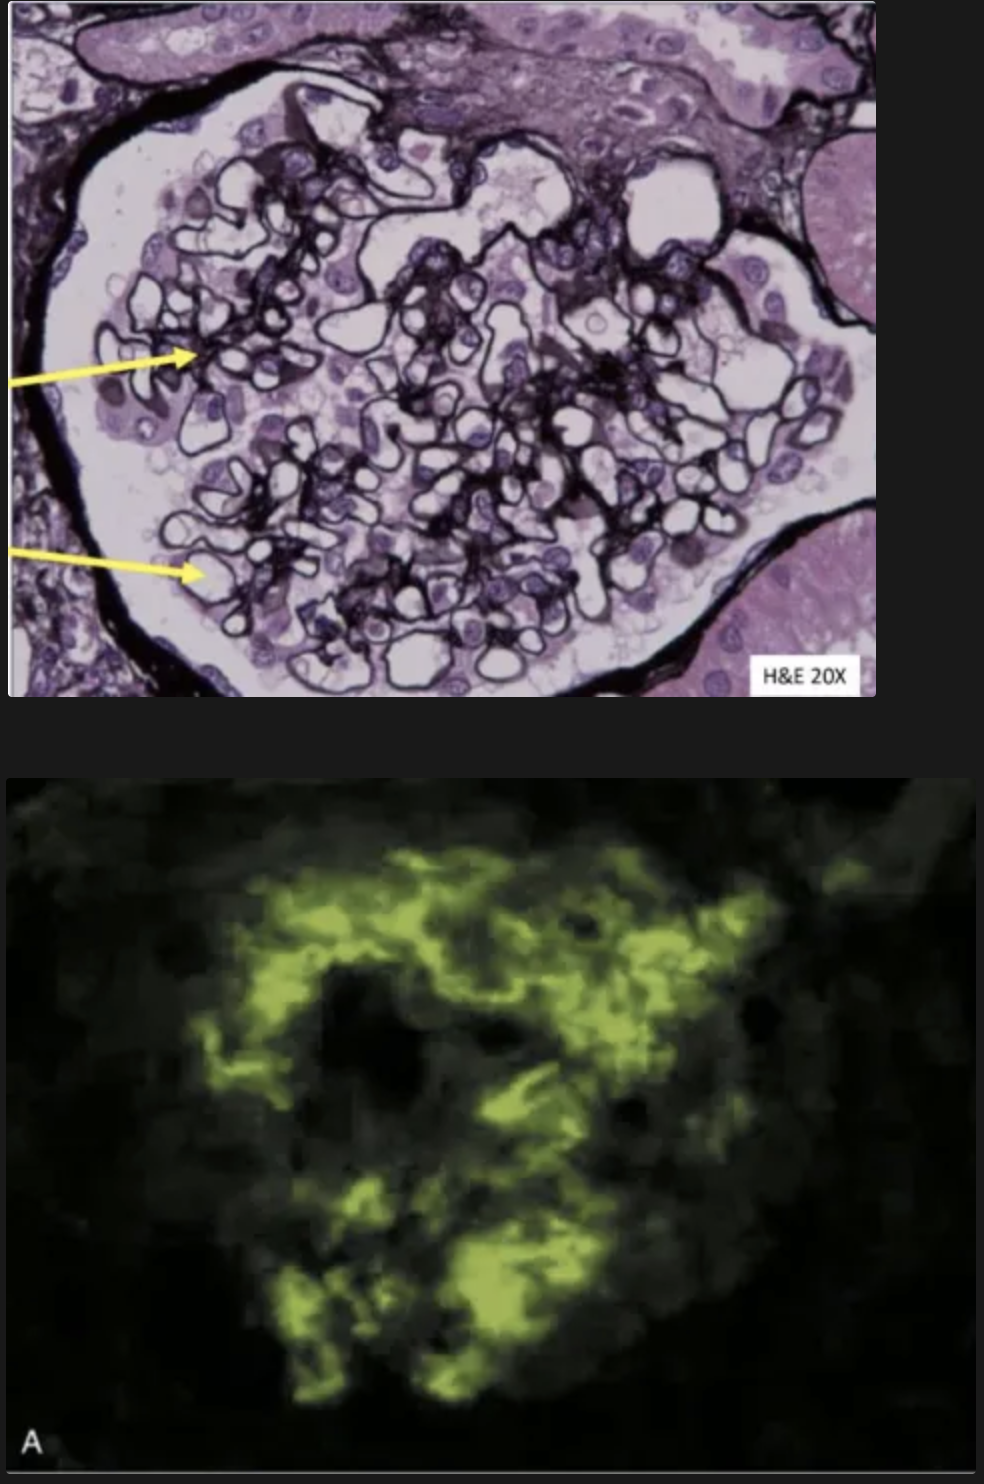

Qué se aprecia en la imágen y a que patologia está asociada?

Necrosis focal y segmentaria y formación de semilunas en el espacio de Bowman.

Enfermedad anti-GBM Good pasture syndrome

Qué se puede ver en la inmunofluorescencia? que patrón sigue? a que enfermedad está asociada?

Se ven: anticuerpos anti-GBM y complemento (IgG, a veces IgA)

Patrón: lineal

Enfermedad anti-GBM (Enfermedad de good pasture)